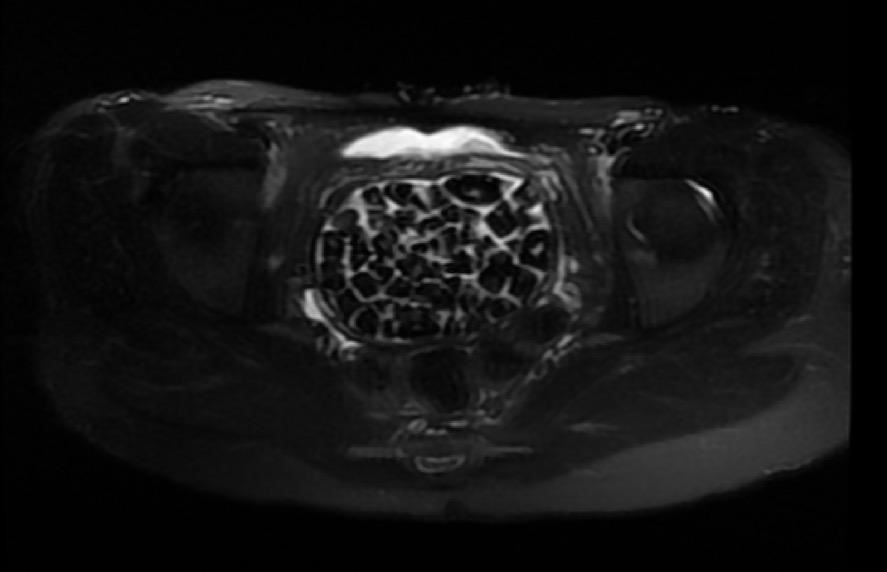

Hastasının durumunu değerlendiren Üroloji Uzmanı Doç. Dr. Erkan Erkan, "Hastamızın 2004 yılında doğduğunu ardından doğar doğmaz ekstrofi vezika dediğimiz 50 binde bir görülen bir anomaliden dolayı art arda ameliyatlar geçirdiğini öğrendik. 10 yaşında yine bir ameliyat geçirmişti, gerekli görüntüleme ve tetkiklerimizi yaptırdık. Normalde mesanesinin olması gereken yerin hemen arka kısmında taşlarla dolu bir kese olduğunu gördük, bunun üzerine ek görüntülemeler; MR çektirdik. Hastamız çelişkili açıklamalar almıştı, kendi radyolojik kliniğimiz ve edindiğimiz konsültasyonlarda taşların mesanede değil vajinal boşlukta oluştuğunu düşündük, bir planlama yaptık.

Genç kızın uzun süredir karın ağrısı çektiğini belirten Jinekolojik Onkoloji Uzmanı Op. Dr. Emin Erhan Dönmez, "Mesane taşları olduğu düşünülerek daha büyük bir hastaneye refere edilmiş. Aramızda mini bir konsey yaparak muayene ettik. Vajen bir hazne görevi görerek orada durağan bir idrar, uzun süre beklediği için idrar içindeki minerallerde çökerek taşlar oluşmuş. Mesanedeki idrarın vajene akmış olabileceği ve vajende göllenen idrar nedeniyle taşların burada oluşacağını düşündük, ameliyatımızı planladık. Ameliyata tanı amaçlı girmiştik, sistoskopi (Mesane gibi idrar yollarını kapsayan kısımlardaki rahatsızlıkların teşhis ve tedavisinde kullanılan endoskopik bir yöntem) dediğimiz ameliyatı Erkan Hocam ile birlikte gerçekleştirdik.

Önce mesaneyi bir görüntüledik, mesane tabanına yaklaşık 2-3 cm’lik bir alandan vajene fistülize olduğunu gördük. Mesaneden vajene geçtiğimiz esnada tüm vajenin taşlarla dolu olduğunu gördük. Tanı amacıyla girdiğimiz ameliyatta her şey de olağan gittiği için tedaviye geçtik. Taşların çıkabileceği kadar bir genişlik sağladık. Daha sonra yaklaşık en büyüğü 2,5 cm boyutlarında olan, irili ufaklı 287 tane taşı ameliyat esnasında çıkarmış olduk. Taşların tekrarlamaması için idrarın göllenmemesi, en azından dışarıya rahatça boşalabilmesi için vajinal rekonstrüksiyonu sağladık. Ameliyatta da herhangi bir problem yaşamadık. Literatürü Erkan Hocam ile birlikte değerlendirmiştik. Primer olarak vajende birikmiş olan bu kadar çok sayıda taşla ilgili bir makale görmedik, rastlamadık" dedi.